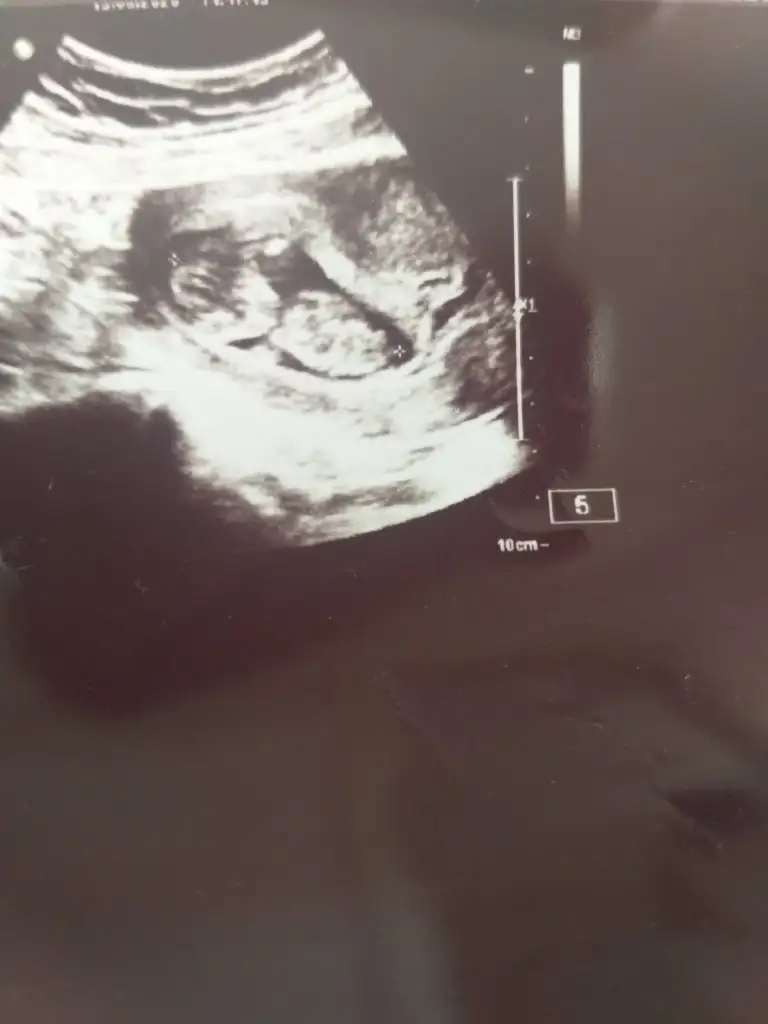

Nub için 12 13 hafta olmalı bacak arası boş görünüyor sanki kıx gibi varsa istediğim haftlarıda paylaşınMerhaba hanımlar bu topiği yeni keşfettim. Düşünenden yardımcı olandan Allah razı olsun inşallah. Ben yurtdışında yaşıyorum ve yaşadığım ülkede 20. Haftadan önce cinsiyet bakmıyorlar. Benim daha bir ayım var ve çok merak ediyorum. Öncelikle rabbim hepimize hayırlı ve sağlıklı evlatlar nasip etsin inşallahBenim en son doktor randevum 2 hafta önceydi 14+ 2 de son aldığım ultrason fotoğrafını ekliyorum. Yorumlayabilir misiniz rica etsem Eki Görüntüle 2652301

Birde elimde 13+5 var ama bakalım belli oluyor mu?Nub için 12 13 hafta olmalı bacak arası boş görünüyor sanki kıx gibi varsa istediğim haftlarıda paylaşın

Kız olabilirMerhaba bu da bizim 14. Hafta görüntümüz bakabilir misiniz?

Erkek sanki 11 12 13 hafta olmalı 14 değil emin değilimMerhaba bu da bizim 14. Hafta görüntümüz bakabilir misiniz?